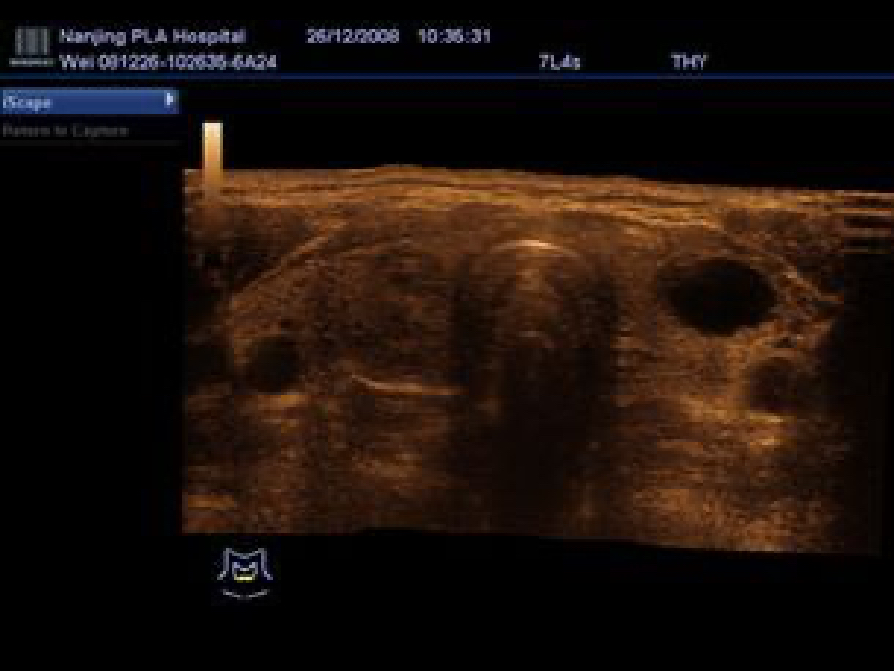

Get a complete and extended view of the anatomical structure through panoramic imaging, coupled with velocity indication and forward/backward scan ability making scanning much easier, smoother and more controllable.